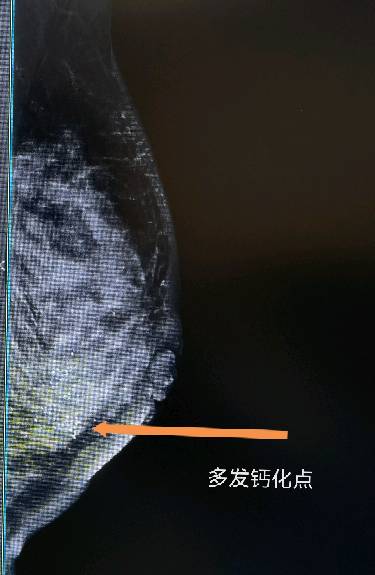

乳腺钙化点 展开>